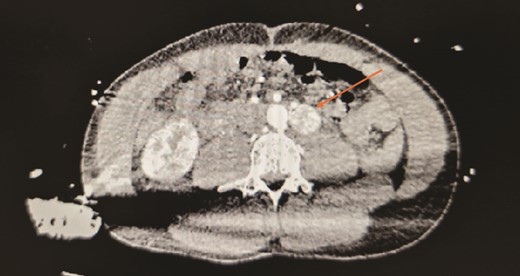

He underwent a robotic excision of his paraganglioma in a right lateral position, using a transperitoneal approach with three robotic ports and one assistant port in the midline. The left colon was mobilized medially, exposing the tumour. After identifying the ureter and gonads, the tumour was dissected freely using a vessel sealer, before removing it in a specimen bag. Operation was uneventful (Figs 3 and 4).

Post tumour removal showed clean base with no active bleeding. No evidence of tissue invasion into peripheral structures.